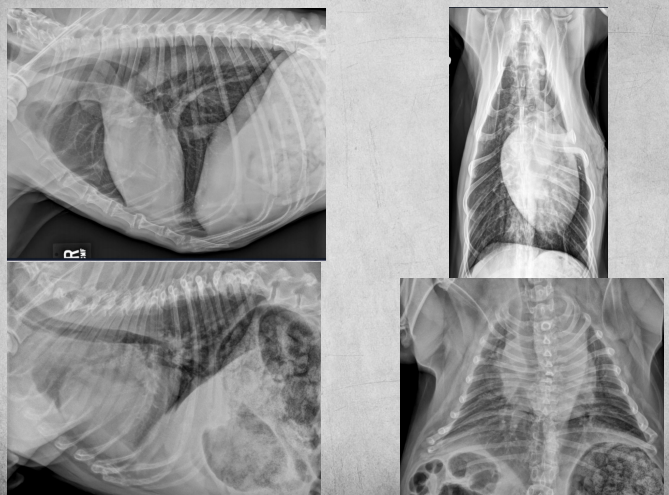

Q

What view is this?

A

DV

13

VD